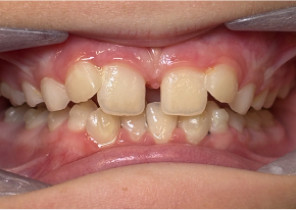

Case Report 2

7 years 11 months old, 24 stages of Invisalign® Palatal Expanders

Courtesy of Dr. David R. Boschken

Pre Invisalign Palatal Expander Expansion

Post Invisalign Palatal Expander Expansion

Post Invisalign Palatal Expander Treatment